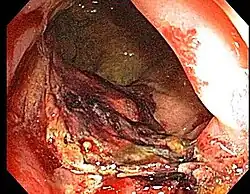

Doctors can diagnose proctitis by looking inside the rectum with a proctoscope or a sigmoidoscope. A biopsy is taken, in which the doctor scrapes a tiny piece of tissue from the rectum, and this tissue is then examined by microscopy. The physician may also take a stool sample to test for infections or bacteria. If the physician suspects that the patient has Crohn's disease or ulcerative colitis, colonoscopy or barium enema X-rays are used to examine areas of the intestine.